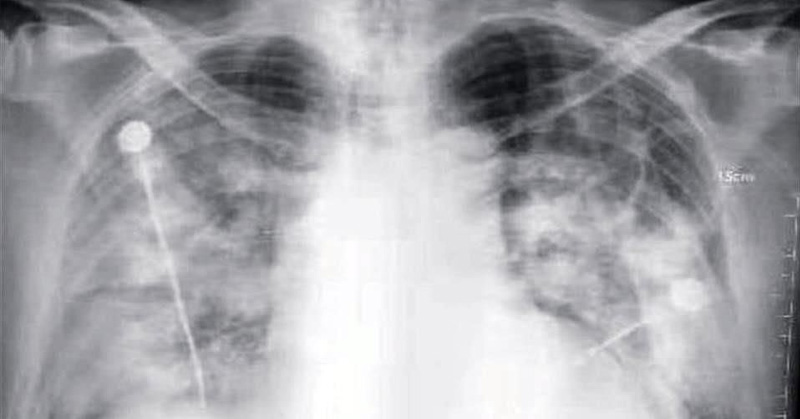

Lo que el coronavirus hace en el cuerpo

Desde tormentas de sangre hasta pulmones apanalados. He aquí un análisis, órgano a órgano, de los daños que el coronavirus (COVID-19) causa en las personas.